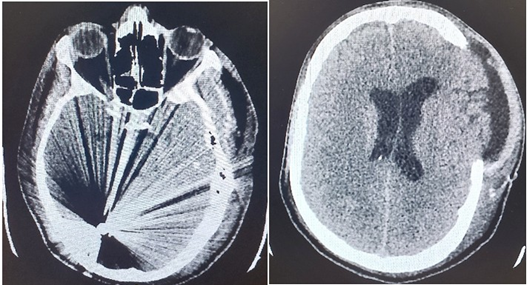

During the neurosurgical procedure, the following stages were performed: Left craniectomy, meningeal section and opening. A small puncture of the anterior part of the sagittal is found where the bleeding is successfully stopped. Wound closure in layers. He was taken under full sedation to the Intensive Care Unit (Figures 1-4, a and b).

Figure 3(a and b): CT Brain scan 13 days after the brain injury and the neurosurgery.